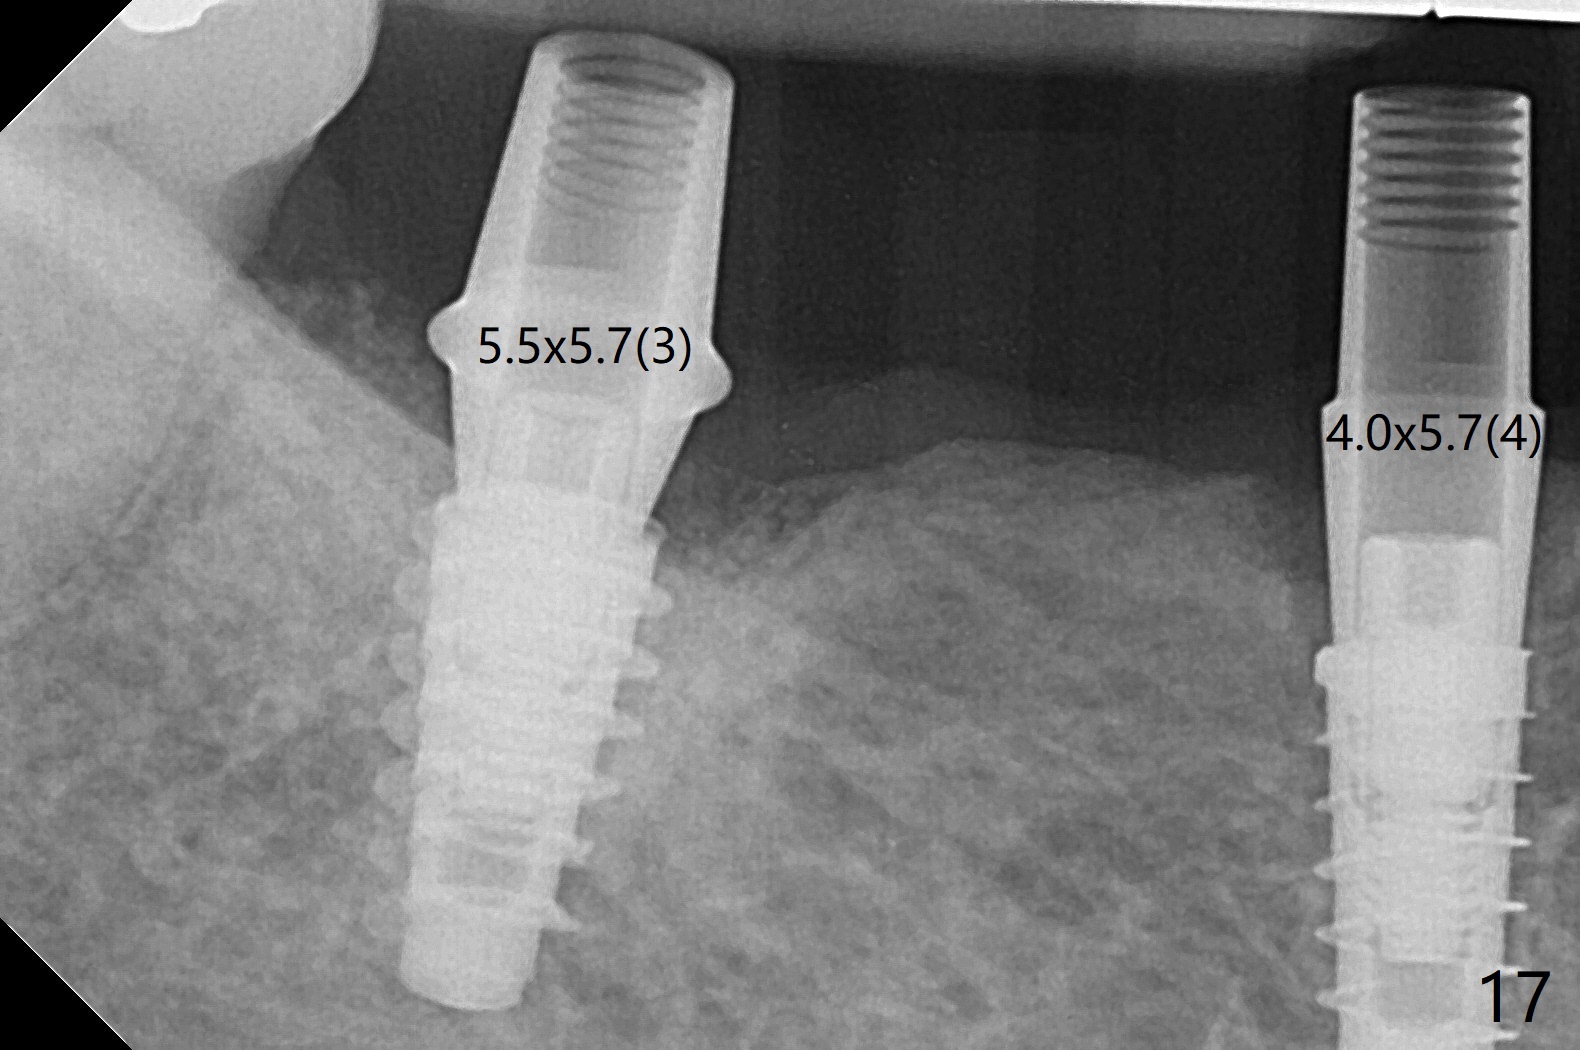

The extraction socket of #31 has a thin septum (Fig.2), which is removed partially with 12 mm bone trimmer (Fig.3). After placement of a 5x9 mm FC implant (~40 Ncm) and 6 mm bone profile drill, a 5.5x4(2) mm abutment is incompletely seated (Fig.5 <) and later is changed to a 4.5x1 mm temporary abutment (Fig.6, 8 T). The latter is used to fabricate a provisional, which in turn supports the distal papilla (Fig.8 *). The gingiva is slightly erythematous immediately post periodontal dressing removal (3 weeks postop, Fig.9). Take CT to confirm whether the cortical drill helps keep the #29 implant lingual. Use a profile drill at #29 if crestal bone loss is not obvious. There is bone coronal to #29 implant 4 months postop (Fig.10). Upon incision, the ridge is rounded (Fig.10'), but the implant appears to be buccally placed (Fig.10'' (post high speed handpiece and 5.5 mm profile drill)). The latter is confirmed by CT (Fig.12, as compared to design (Fig.11)). In spite of use of cortical drill coronally, the implant is still deviated buccally due to contrasting deferential bone density linguobuccally (Fig.13). By comparison, there is no such bone density differential involving an immediate implant at #31; the implant is placed in the socket without contacting the buccal or lingual cortices (Fig.14). The final implant is the same as expected (Fig.15). To avoid implant deviation in the lower premolar region, leave the root in place until osteotomy is finished. Five months postop, the temporary and healing abutments at #31 and 29 change to pair ones (Fig.16). Since there is limited clearance from the crestal bone, smaller abutments are used with the apparently same degree of seating (Fig.17). The abutments are prepared due to the mesial (#31) and buccal (29) tilt before impression.